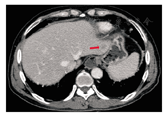

结直肠癌伴同时性肝转移术前新辅助治疗目的在于清除系统内休眠的肿瘤细胞,降低复发风险,同时缩小肿瘤,为手术创造条件,判断肿瘤对化疗的敏感性,为术后化疗提供参考依据。另一方面,对于同时性肝转移的病例,手术的方式目前有两种,即同期切除原发灶及转移灶,或是分期切除病灶,分期切除可以先切除原发灶,也可以先切除肝转移灶。对于手术方式的选择,目前尚无明确的定论。该例患者行选择分期切除的策略,首先切除转移灶,但患者术后1月即出现残肝新发病灶,见图3。其原因可能是由于患者术前肝脏多发转移病灶,化疗使得微小病灶消失,逃离手术清扫范围;或是残留病灶继续生长。